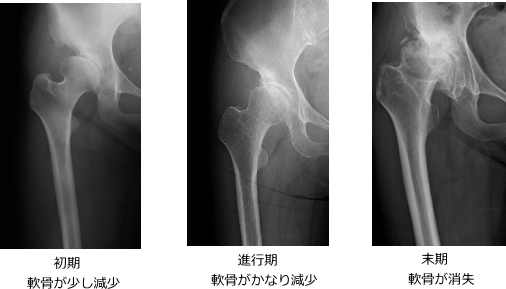

股関節の軟骨が徐々にすり減り、関節が変形していく病気です。

問診と身体診察、X線検査を中心に行います。

軟骨の厚みはX線では見えませんが、関節の隙間の狭小化で診断できます。

必要に応じて、CT・MRI検査で詳しく確認します。